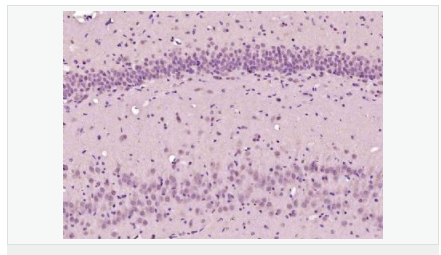

| 產(chǎn)品介紹 | Involved in the formation and segmentation of paraxial mesoderm. Has the regulatory capacity to specify ventrolateral (including future paraxial), but not dorsal (future axial), mesoderm phenotypes. Seems to be an upstream regulator of at least some elements of the Notch and Delta signaling pathway. Function: Involved in specifying the paraxial, but not dorsal, mesoderm. May regulate the expression of T-box transcription factors required for mesoderm formation and differentiation (By similarity). Subcellular Location: Nucleus. Similarity: Contains 1 basic helix-loop-helix (bHLH) domain. SWISS: A6NI15 Gene ID: 343930 Database links: Entrez Gene: 343930 Human Omim: 612209 Human SwissProt: A6NI15 Human Unigene: 705359 Human Important Note: This product as supplied is intended for research use only, not for use in human, therapeutic or diagnostic applications. |